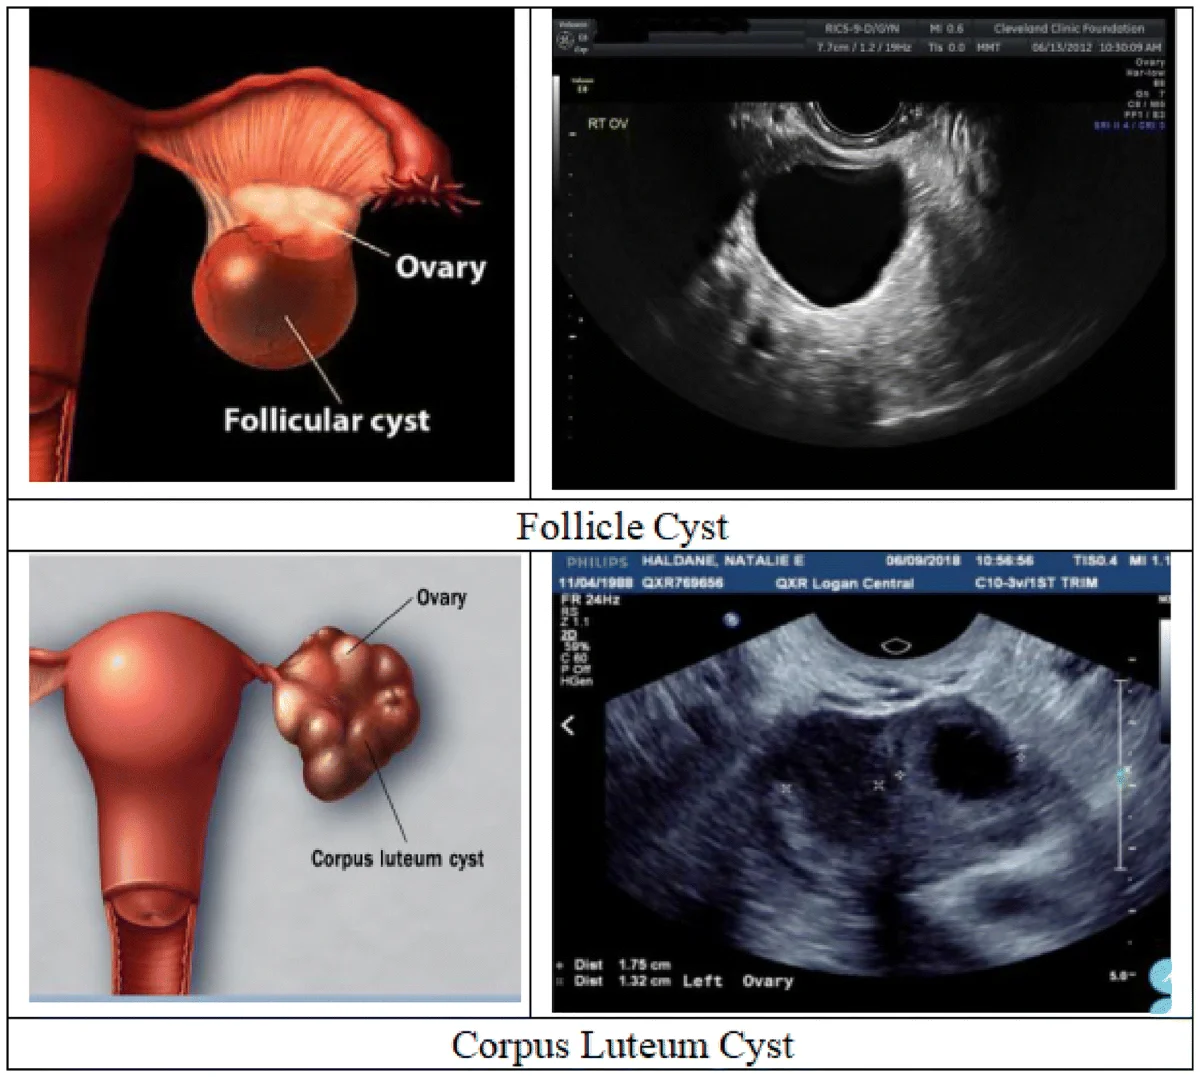

Ovarian Cysts

Ovarian cysts are fluid-filled sacs in the ovaries. While many cysts resolve naturally, some may cause pain, irregular cycles, or complications and require medical or surgical management.